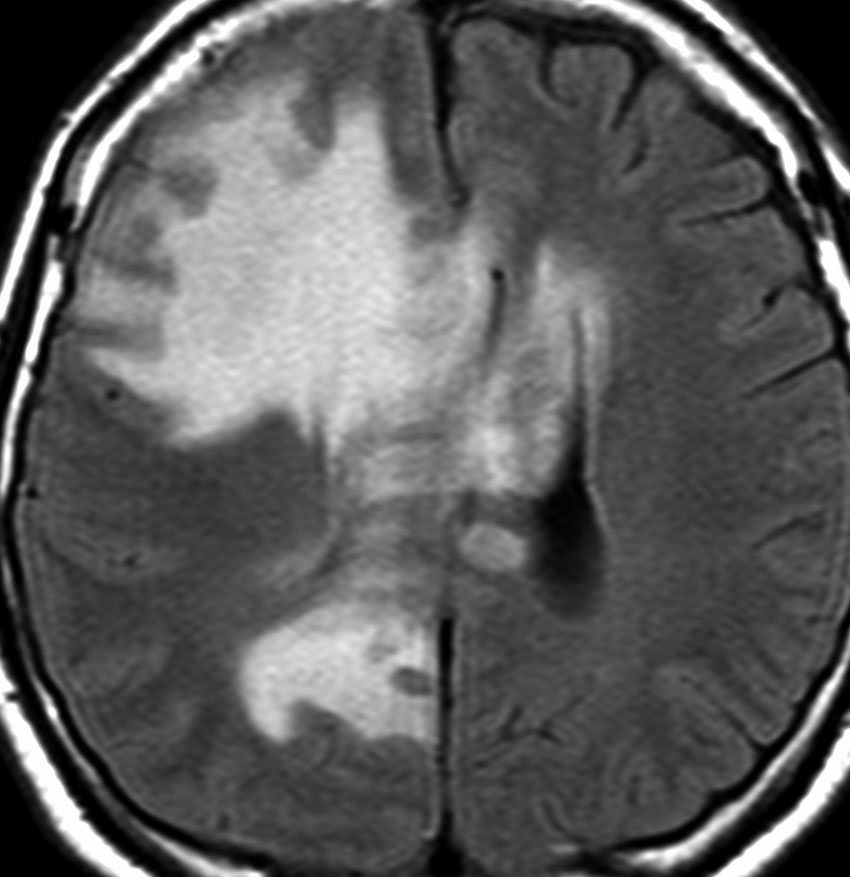

皮膚病変で診断されていた患者さんの同時多発性脳病変

60代女性で,皮膚結節がB cell lymphoma (neoplastic angioendotheliosis)がありました。1年後に急性の認知機能障害と歩行障害がありMRIで発見されたものです。SPECT, PET検査では多発性虚血性病変です。生検手術でIVLの診断が得られました。

左は発症時,右はCHOP化学療法1コース後のT2強調画像です。化学療法で寛解しました。